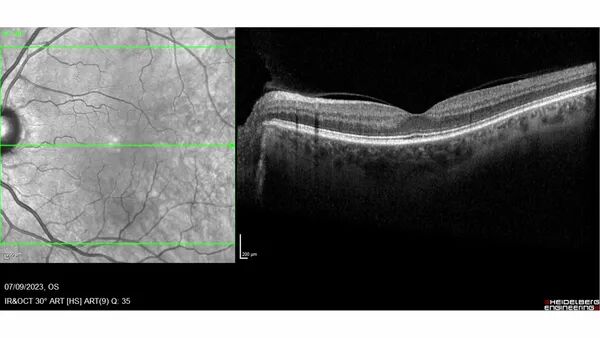

Cas clinique : surveillance et détection précoce avec Odysight

Une patiente âgée de 70 ans, présentant une acuité visuelle de 20/25, a été initialement examinée le 21 février 2024. Son suivi a été renforcé grâce à Odysight, une solution de télésurveillance ophtalmologique permettant de détecter précocement des signes d'aggravation. Dernière visite le 25 novembre 2024, et rendez-vous prévu en avril 2025.

Nous avons pu identifier des signes évocateurs d’une activité exsudative de néovaisseaux choroïdiens. Grâce à cette alerte, la patiente a été convoquée rapidement pour un rendez-vous médical le 6 janvier 2025, soit trois mois avant son rendez-vous.

Cette intervention précoce a permis d’optimiser la prise en charge thérapeutique et d’améliorer le pronostic visuel de la patiente. En facilitant le suivi à distance et en signalant les évolutions pathologiques en temps réel, Odysight s’affirme ainsi comme un allié précieux dans la gestion de la DMLA exsudative.

Conclusion

L’OCTA et les solutions de télésurveillance comme Odysight jouent un rôle clé dans la détection et la prise en charge précoce des pathologies rétiniennes. En améliorant la réactivité face aux signes d’aggravation, ces technologies contribuent à préserver la vision des patients et à optimiser leur suivi thérapeutique.